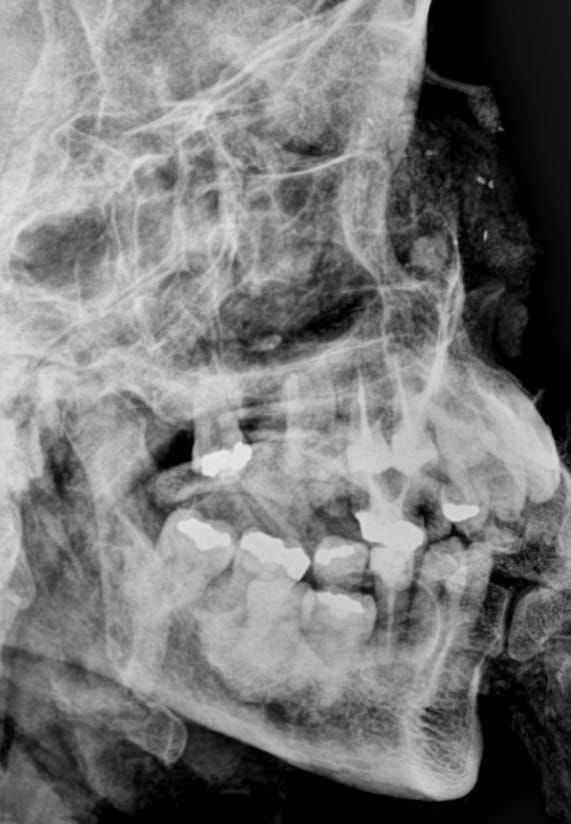

De acordo com os odontolegistas, os dois corpos carbonizados tiveram seus arcos dentários cuidadosamente examinados e radiografados. Desde ontem, a equipe do setor de Odontologia Forense vinha trabalhando, realizando várias análises para garantir uma resposta oficial para os familiares das vítimas.

A identificação da vítima foi possível através da comparação odontolegal entre os trabalhos odontológicos verificados no exame dos arcos dentários do corpo carbonizado e nas radiografias post mortem obtidas deste mesmo corpo no scanner de cadáveres com os dados fornecidos pelo cirurgião-dentista.

A Identificação de Maria de Lourdes foi possível através da comparação odontolegal entre os trabalhos odontológicos verificados no exame dos arcos dentários do corpo carbonizado e nas radiografias post mortem obtidas deste mesmo corpo no scanner de cadáveres com os dados fornecidos pelo cirurgião-dentista.

Já a segunda vítima, o menor Rafael Nilo dos Santos Nunes, foi identificada através de um trabalho minucioso de estimativa de idade realizado também com o auxílio de radiografias post mortem. Com a conclusão dos exames foi possível emitir as declarações de óbito com a identificação oficial das vítimas.